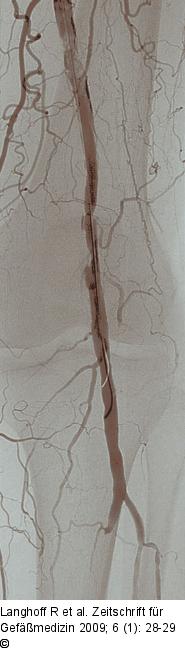

Abbildung 3: PTA

Ergebnis nach PTA mit spiraligen Dissektionen